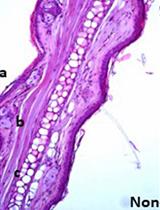

Escherichia coli Outer Membrane Vesicle Immunization Protocol and Induction of Bacterial Sepsis